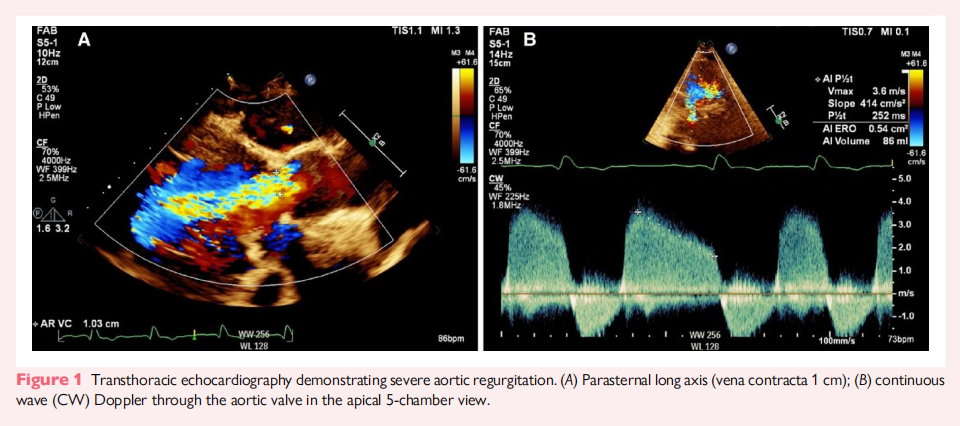

2023 年,患者因呼吸困难再次就诊,TTE 评估显示严重 AR,左心室功能进一步恶化,LVEF 仅为 15%(图1)。CT 评估显示主动脉瓣无钙化,新生瓣环(neo-annulus)面积为 660 mm²,左冠状动脉开口高度较低,仅 7.1 mm(图2)。Valsalva 窦较狭窄,平均直径 31 mm,窦管连接区(STJ)同样狭窄(28 mm),高度为 24 mm。由于二次开胸手术风险较高,心脏团队一致同意采用经导管主动脉瓣置换术(TAVR)。患者的瓣环过大,无法使用 27 mm Trilogy 瓣膜,因此选择了球囊扩张型经导管瓣膜(THV),主要考虑其良好的冠状动脉通路可及性,并且适用于未来可能的二次 TAVR 介入。

术前超声心动图(TTE)显示,该患者的原生主动脉瓣为三叶瓣,瓣叶轻度增厚但无钙化,同时左心室(LV)功能受损,射血分数(LVEF)为 45%。冠状动脉造影未见明显冠状动脉病变。术后,该患者出现心输出量下降,冠状动脉造影提示右冠状动脉(RCA)开口医源性狭窄,可能是右冠纽扣(coronary button)重新植入时造成的。随后,患者接受了再次开胸手术,并采用大隐静脉移植至 RCA 进行血运重建。术后TTE显示,患者左心室功能严重受损(LVEF 30%),并存在中度 AR。